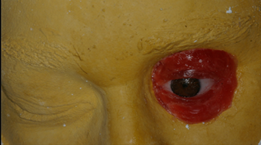

Medication and post-operative care. The patient was administered 875 mg of oral amoxicillin every 12 hours for 7 days. As analgesia, 600 mg of oral ibuprofen every 8 hours for 3 days was prescribed. Postoperative assessment took place seven days after the surgical procedure, when sutures and dressing were removed, and then monthly for 4-6 months. After this period, the osseointegration of the implants was assessed and the prosthesis was made (Fig. 5). The criteria used to assess osseointegration were: absence of pain, dysesthesia and immobility15).

The clinical case described herein presented mild inflammation (Holgers 1) in the second biannual check-up appointment. Therefore, the patient was encouraged to improve hygiene practices. The patient was very cooperative, thus there was good peri-implant tissue response, with no complications, two years after the implants had been placed. The successful outcome of this clinical case by placing an implant-supported orbital prosthesis is consistent with what the abovementioned authors have reported in terms of a tapered dental implant design, with a reduced platform. These implants are suitable for a low density and limited width region such as this.